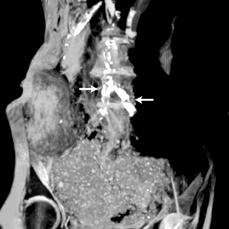

While the Horus study has previously reported atherosclerotic vascular calcifications on CT scans in ancient Egyptians, the Horus team’s new study compared patterns and demographic characteristics of this disease among Egyptians from both ancient and modern eras.[1] The authors compared the presence and extent of vascular calcifications from whole-body CT scans performed on 178 modern Egyptians from Cairo undergoing positron emission tomography (PET)/CT for cancer staging to CT scans of 76 Egyptian mummies (3100 BC to 364 AD). Patients undergoing cancer staging were selected for the study because these scans had already been completed for this group of patients as part of their cancer care.

The mean age of the modern Egyptian group was 52 years (range 14 to 84) vs. estimated age at death of ancient Egyptian mummies at 36 years (range 4 to 60). Vascular calcification (evidence of atherosclerosis) was detected in 108 of 178 (61 percent) modern patients vs. 26 of 76 (38 percent) mummies, with vascular calcifications on CT strongly correlated to age in both groups. In addition, the severity of disease by number of involved arterial beds also correlated to age, and there was a very similar pattern between the two groups.

“The CT scans show a surprising similarity in the amount and distribution of atherosclerotic calcifications between ancient Egyptians and men and women living in the U.S. today,” said James Sutherland, M.D., co-author and radiologist at Saddleback and Orange Coast Memorial in California. “This should lead to re-evaluation of the root causes of atherosclerosis and could lead to entirely new avenues of prevention and early treatment.”